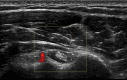

Diagnosis is crucial in decision-making when treating a patient with shoulder pain. Ultrasound is also very important in the diagnostic and therapeutic pathway, especially when surgery is being considered. This article outlines the diagnostic pathway using the patient's history, physical examination and ultrasound examination. It is important to correlate the clinical assessment with the imaging signs. It is also important to treat the patient and not the images as there may be abnormalities detected on imaging that are not symptomatic. The article covers the important diagnosis of subdeltoid subacromial bursitis, glenohumeral joint capsulitis, calcific tendinosis, acromioclavicular joint osteoarthritis and long head of biceps tendinosis. It will guide the reader in how to use the findings to treat, using ultrasound-guided injection and other techniques, including steroid injections, hydrodilatation, barbotage and extracorporeal shockwave treatment. These are discussed with the knowledge from over 30 years of experience with a literature review evidential support. I have included tips to make these procedures more effective in treatment and final outcome. There is discussion regarding the use of steroid injections in the presence of a rotator cuff tear and how to proceed if the patient has more than one disease process. The sensible use of steroids and local anesthetics are included, bearing in mind that lidocaine and high concentrations of long-acting local anesthetics are chondrotoxic and should not be injected into joints.